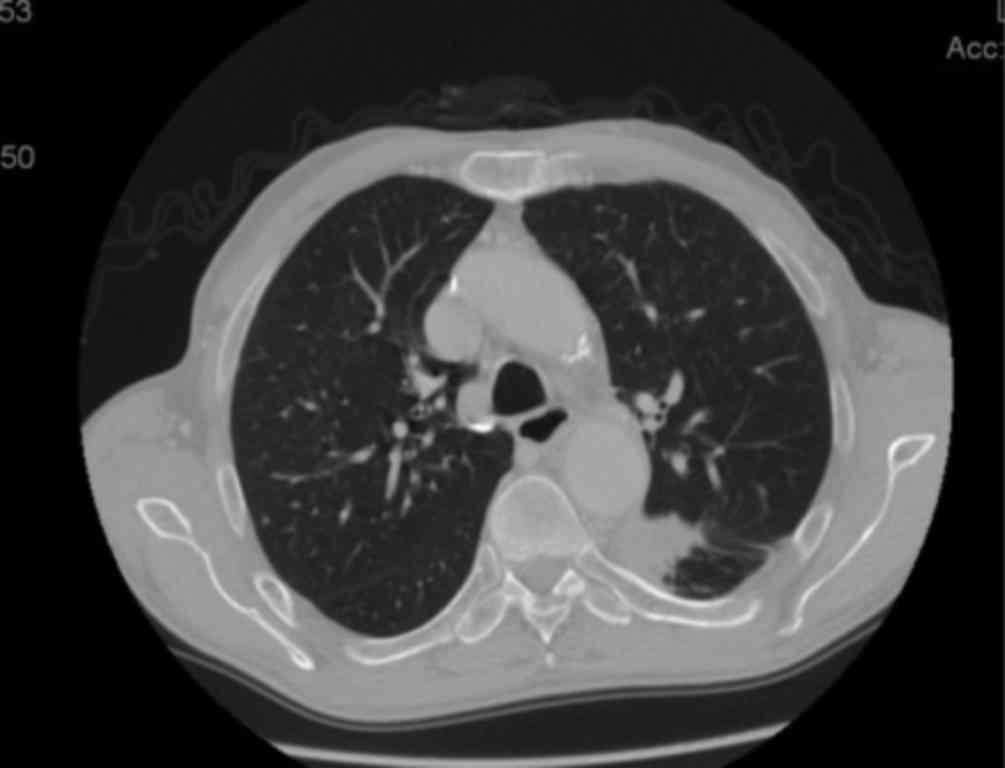

Long-term survival in a patient with metastatic squamous cell lung carcinoma: A case report

Non-small-cell lung cancer (NSCLC) is the most common malignancy in industrialized countries, with a 5-year survival rate of only ~15%, as the majority of the patients have advanced-stage disease at diagnosis and the treatment options are limited. Squamous cell carcinoma the second most frequent type of NSCLC and is closely associated with cigarette smoking. We herein present the case of a 72-year-old male smoker, diagnosed with stage IV squamous cell lung carcinoma, with a solitary brain metastasis. After the diagnosis, stereotactic radiotherapy was performed on the brain metastasis. Following radiotherapy, chemotherapy with carboplatin + paclitaxel was initiated. However, after 2 cycles of chemotherapy, disease progression in the lung was observed. Therefore, second-line treatment with pemetrexed was started, which was discontinued after 2 cycles due to further disease progression. Third-line treatment with erlotinib was then administered, with notable benefit, as the patient remains alive after 6 years of treatment with a good performance status. The mutation status of EGFR was unknown.

Figure 1

Figure 2

Figure 3

Figure 4